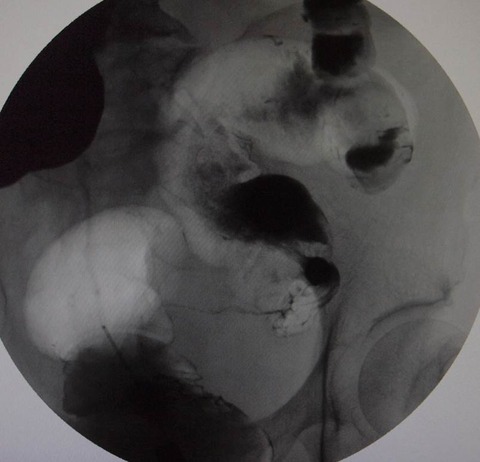

大腸癌イレウス例49例のうち26例では,入院後速や 表4 大腸癌の組織学的リンパ節転移 表5 大腸癌イレウスにおける手術術式 ( )二期的手術 79(959) かに救急手術が行われた。残り23例ではlong tubeに よる腸管内容物の吸引,水分・電解質の補正,高カロ. 閉塞性大腸癌は,全大腸癌の3. 1~15. 8%と比較的高頻度に認め 1) ,緊急処置を必要とするoncological emergencyな状態であり,イレウス解除とともに大腸癌の根治性も考慮しなければならない.閉塞性大腸癌症例の多くは一般に全身状態不良であり,術前検査や十分. 大腸癌イレウス例49例のうち26例では,入院後速や 表4 大腸癌の組織学的リンパ節転移 表5 大腸癌イレウスにおける手術術式 ( )二期的手術 79(959) かに救急手術が行われた。残り23例ではlong tubeに よる腸管内容物の吸引,水分・電解質の補正,高カロ. 癌1例,上行結腸癌1例,膵臓癌1例,原発不明 癌1例であった.すべての症例が癌性腹膜炎によ る消化管閉塞を伴っていた.7例中4例に水溶性 造影剤による消化管造影を行い,胃癌3例,膵臓 癌1例は消化管の完全閉塞を認めた.症状の表記.

左側大腸癌イレウス治療における経肛門イレウス管の適応と限界について後方視的に検討した。2006 ~2011年に当科で手術治療を施行した左側大腸癌イレウス59症例を経肛門イレウス管減圧群( dc群) と非減圧群(ndc群)の2群に分け治療成績を比較した. 「大腸癌治療ガイドライン 2016年版」「大腸癌取扱い規約 第8版(2013年)」より、内容の更新をしました。4タブ形式に変更しました。 2018年02月21日 「大腸がん」のタイトルを「大腸がん(結腸がん・直腸がん)」に変更しました。 2016年01月06日. しかし治癒切除例に. 限れば,同じ stage の非イレウス症例と比較して予後. に差 がなかったとする報告もある 10)14)17)。実際の手. 術に際しては,一期的 .

がんの進行で大腸が閉塞すると、腸管内に便や腸液やガスなどがたまってお腹が 緊急手術以外に「イレウス管」と呼ばれるチューブを鼻や肛門から挿入し、 . 大腸ステント留置が長期予後に与える影響については様々な報告があり,エビデンスが不十分であるのが現状である。2012 年7 月~2017 年9 月の間に根治手術可能な左側大腸癌イレウスに対しbridge 大腸癌イレウス 予後 to surgery(bts)として大腸ステント留置後に手術を施行した36 例(bts 群)と,2012 年6 月以前の大腸ステント. 疾患の解説. 膵がんは50~70歳、特に高齢の男性に多いがんです。膵臓には強力な消化酵素(アミラーゼ、トリプシン、リパーゼなど)を分泌する外分泌腺と、ホルモン(インスリンなど)を分泌する内分泌腺があります。.